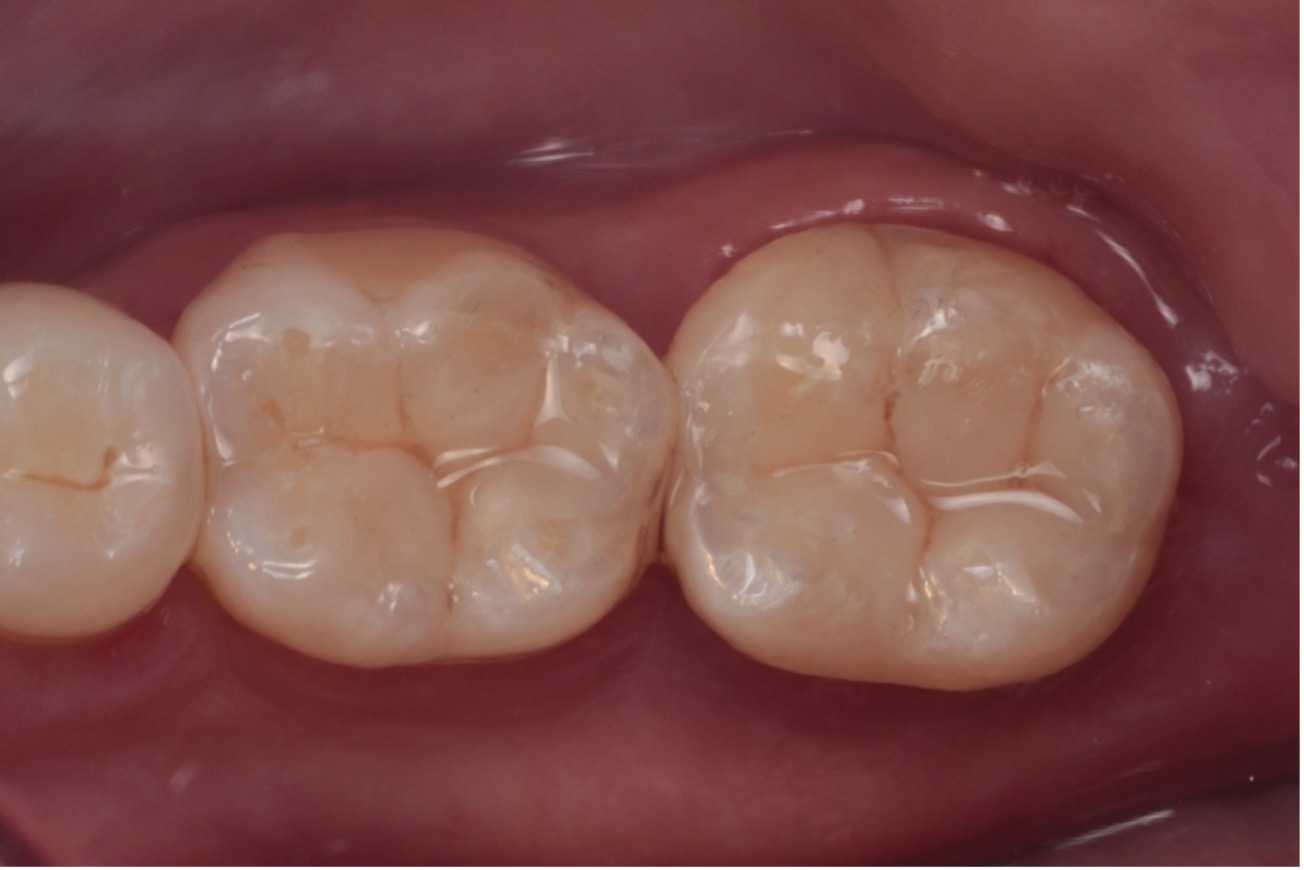

O resultado clínico demonstrou excelente integração estética, funcionalidade adequada e satisfação por parte da paciente (Figura 13).

Figura 13 – Resultado final